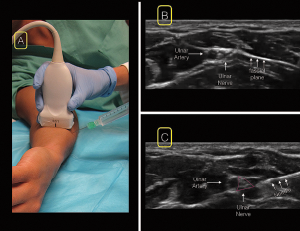

Figure 5. For the ulnar nerve block, position the linear ultrasound at the wrist over the ulnar artery (A). Scan proximally until the nerve separates from the artery in the ulnar direction in the mid-to-proximal forearm (B). insert your needle from the ulnar (medial) aspect of the probe (A&C).